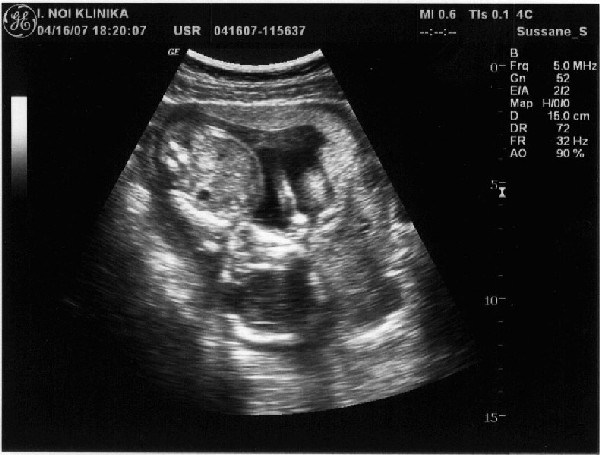

Szóval mi is voltunk genetikai UH-n és minden rendben volt. A hölgy nem volt túl kedves és semmit nem magyarázott el és kicsit gyors is lett az egész, de nem panaszkodom, mert nem lettek olyan rossz élményeim, mint egyeseknek.

Viszon a mi kis drágánk még titkolódzik egy picit, a lába közé kapta a köldökzsinórt :)

Pár kép róla:

Az első képen cumizik, remélem ti is látjátok. :) Kicsit összekeverhető melyik a feje és a pocakja, de annnyit segítek, hogy fejjel lefelé van :).